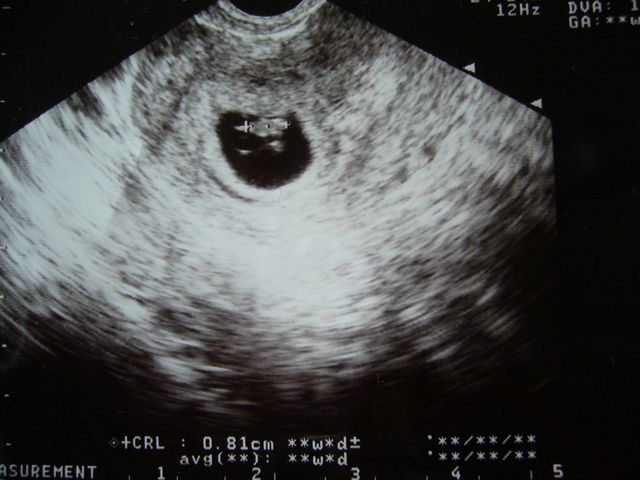

妊娠初期 胎嚢が小さいと言われてから心拍確認までの記録 よっちのパピルス帳

情緒不安定 妊娠初期のエコーと心拍確認ができた6週目の様子 えびママの人生楽しむべさ